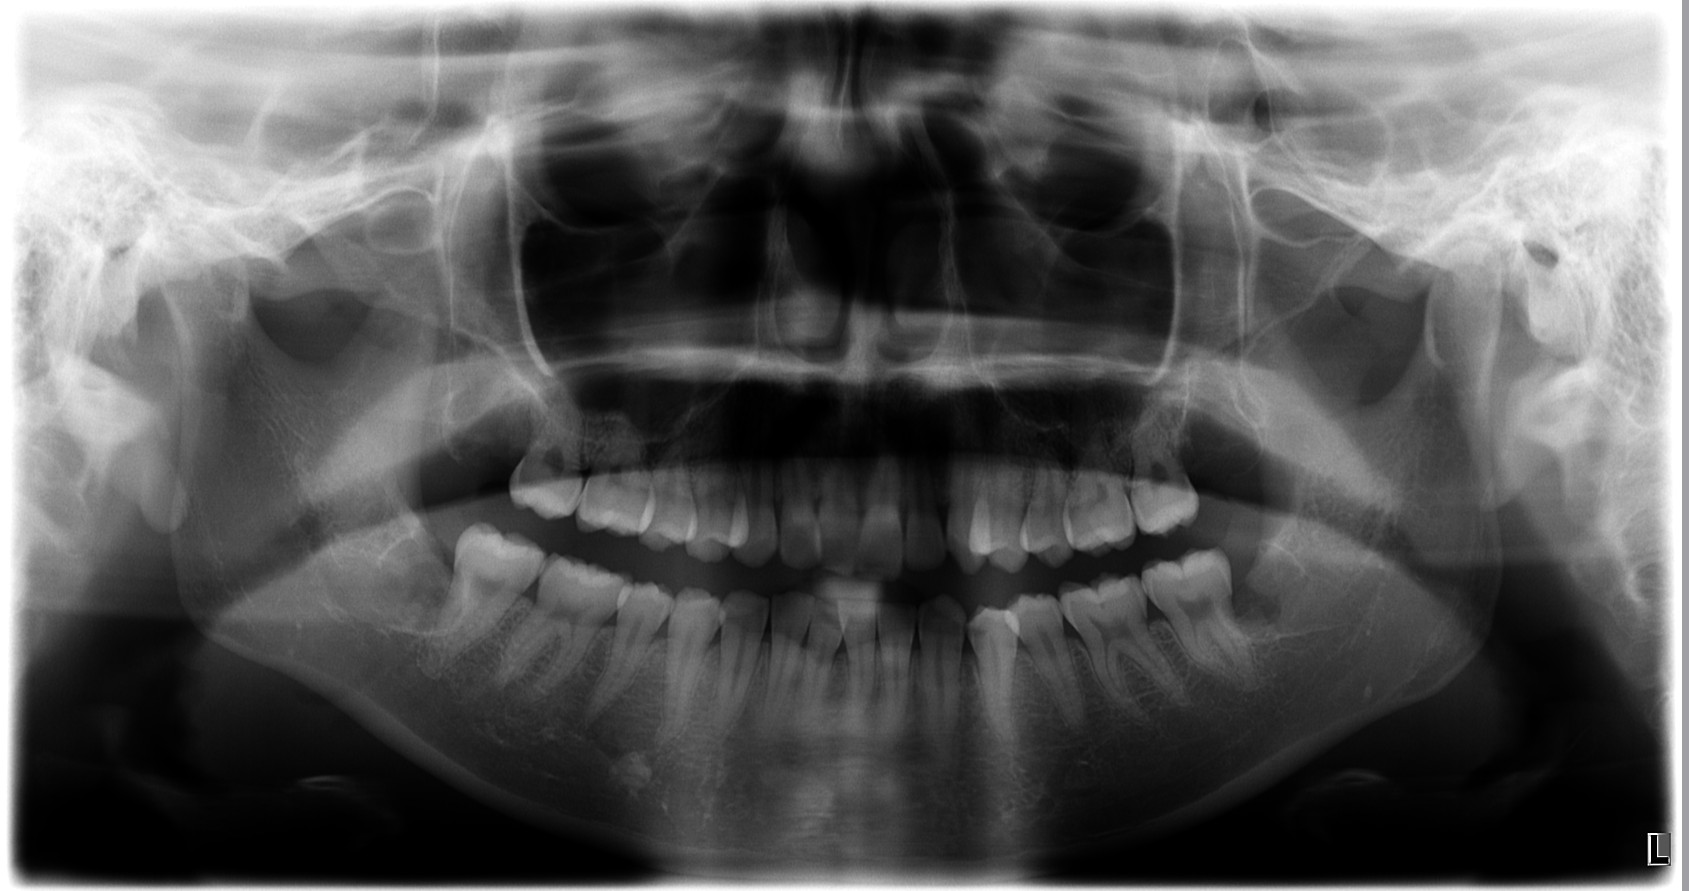

治療後

パノラマX線写真で、上下とも下顎管および上顎洞との近接が確認されました。

(※以下の画像は実際の術前・術後のパノラマ写真を掲載)